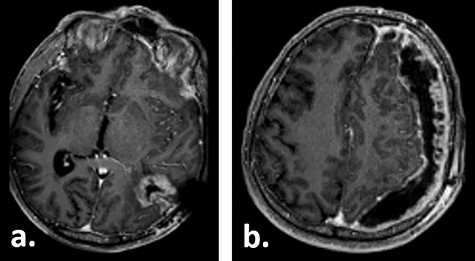

Gadolinium-enhanced T1-weighted axial MRI of the patient 10 weeks after tumour resection demonstrating the resection cavity (a) and new subdural fluid collection (b).

Fifteen weeks after tumour resection and 4 weeks after hygroma evacuation, the patient presented again with concentration loss, fatigue and a moderate right-sided hemiparesis. A new CT scan revealed a strongly progressive subdural hygroma with a 3-mm-thick subdural membrane. The hygroma was evacuated through the same burr hole; however, due to an unsatisfying hygroma regression, a subduro–peritoneal shunt for permanent hygroma drainage was implanted subsequently. During these both procedures, a thick greyish subdural membrane was noticed, but no tissue samples were taken. Despite the volume reduction of the hygroma, its membrane still caused a considerable mass effect. Few days after the last surgical procedure, a cerebral MRI was performed following the tumour follow-up protocol. On this imaging, the subdural membrane over the left hemisphere presented as an inhomogeneous contrast-enhancing lesion with irregular contours (Fig. 3).

Gadolinium-enhanced T1-weighted axial MRI of the patient 16 weeks after tumour resection demonstrating the resection cavity (a) and progressive subdural fluid collection with the newly occurred contrast-enhancing membrane (b).